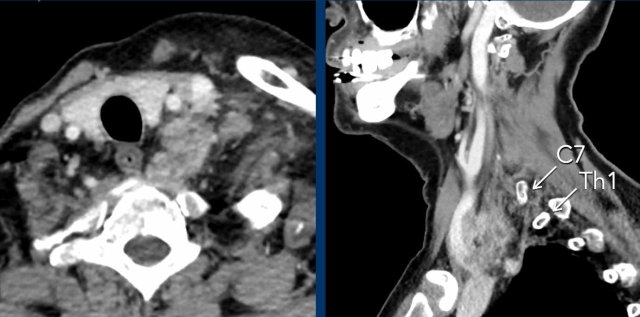

Subsequently a CT of the neck and chest was performed, which showed a prevertebral mass at the level of C7-Th1.

This is the exact location of the inferior cervical ganglion.

A mass in this location explains the Horner on the left.

The CT at admission showed fractures of the transverse process of C7 and of the first rib (arrowheads).

On the CECT there was contrast extravasation indicating active bleeding (circle).